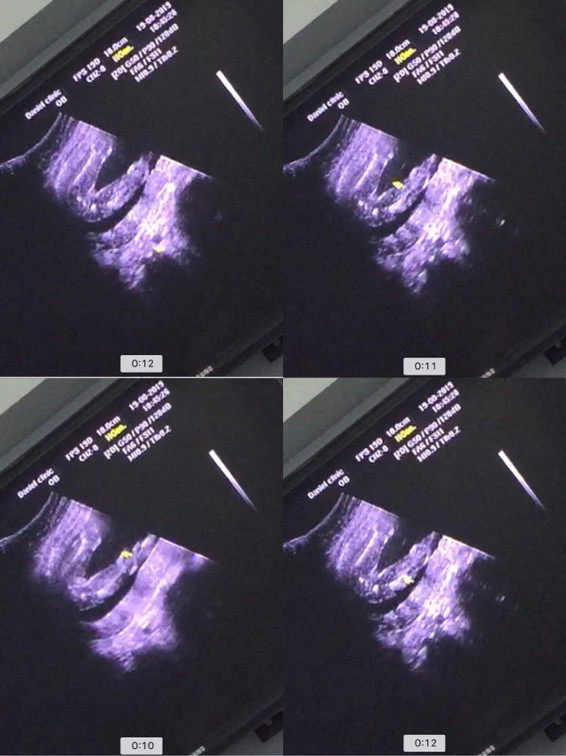

ภาพซาวด์เพศลูกค่ะ

ขอดูภาพซาวด์เพศลูกของแม่ๆหน่อยค่ะ ว่าเห็นเป็นแบบไหน ได้เพศอะไรบ้าง ?

หมอบอกผู้หญิงค่ะ

ลูกสาวค่า😘

เพศหญิงค่ะ😍

ผู้ชายคะ 👶🏻

ลูกสาวจ้า

ลูกสาวค่ะ